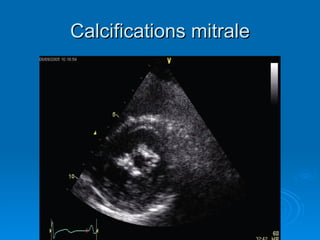

Étiologies Le RM est presque toujours d’origine  streptococcique ,  post RAA  presque 99% cas Cause plus rare: RM par  calcification anneau mitral RM  congénital

Anatomie Pathologie Les lesions de l’appareil mitral se constituent progressivement en 5 – 10 ans  suivant poussée RAA: Épaississement valvulaire Hypertrophie rétraction des cordages Soudure des commissures Calcification de anneau et de la valve

Calcifications mitrale

Étiologies Le RMest presque toujours d’origine streptococcique , post RAA presque 99% cas Cause plus rare: RM par calcification anneau mitral RM congénital

Anatomie Pathologie Leslesions de l’appareil mitral se constituent progressivement en 5 – 10 ans suivant poussée RAA: Épaississement valvulaire Hypertrophie rétraction des cordages Soudure des commissures Calcification de anneau et de la valve